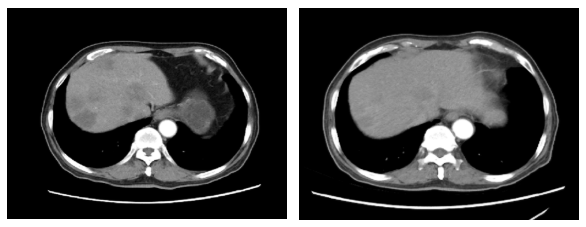

2020.1.5影像学评价:腹部CT:肝脏多发结节,较前增多增大,考虑进展(图3)。

图3. 腹部CT(左:2019.11.18,右:2020.1.5)